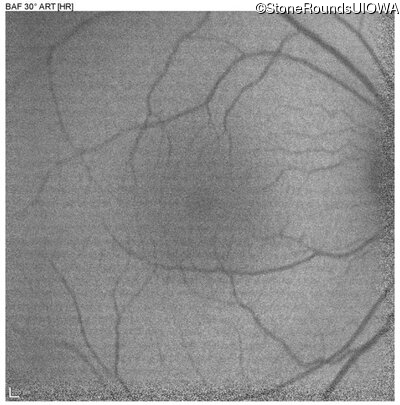

Blue Autofluorescence - Left - 20/20 -1

Exemplar